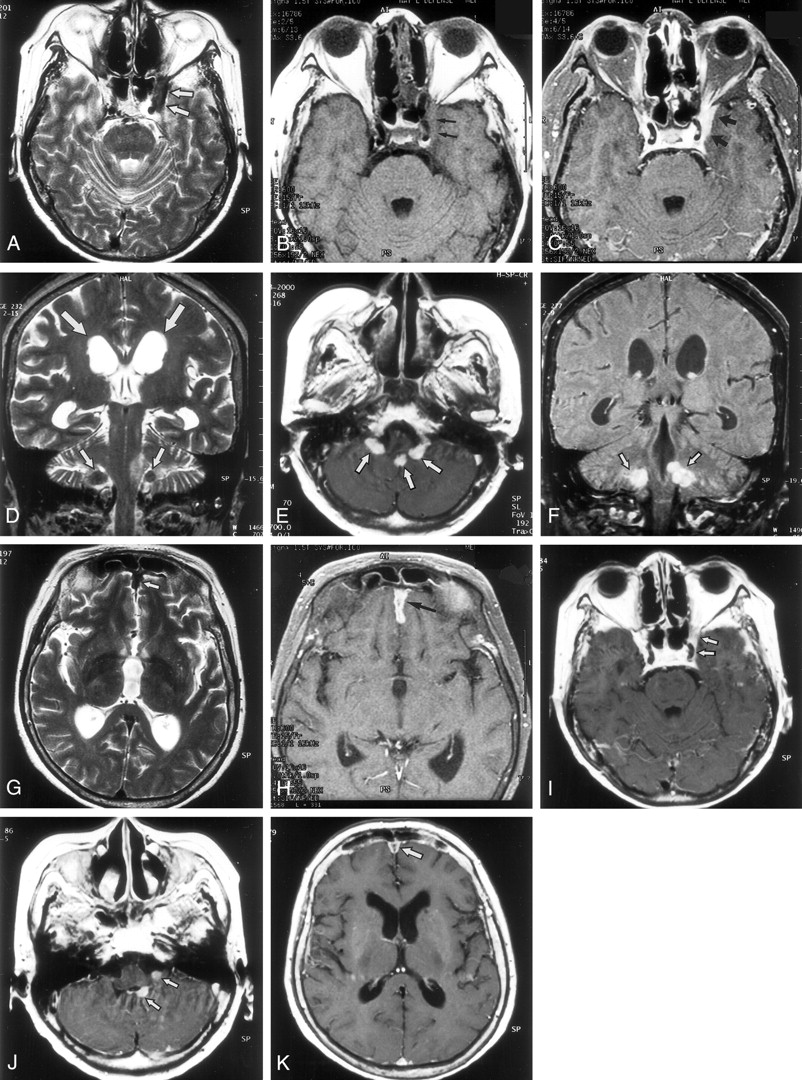

MR findings in a 54-year-old woman with CSS.

A, Axial T2-weighted image (3500/120/2 [TR/TE/excitations]) shows a hypointense plaquelike lesion (arrows) involving dura of the left cavernous sinus and superior ophthalmic fissure.

B, Axial T1-weighted image (600/15/1) shows that the lesion (arrows) is isointense to brain.

C, Axial contrast-enhanced T1-weighted image (600/15/1) shows abnormal enhancement of the lesion (arrows) around the left cavernous sinus and the superior ophthalmic fissure.

D, Coronal T2-weighted image (3500/120/2) shows hypointense nodules (small arrows) in the bilateral lateral recess of the fourth ventricle. Dilatation of the lateral ventricle is shown (large arrows).

E, Axial contrast-enhanced T1-weighted image (600/15/1) shows enhancing nodular lesions in the fourth ventricle, extending to bilateral lateral recess (arrows).

F, Coronal contrast-enhanced T1-weighted image (600/15/1) shows enhancing nodular lesions (arrows) in the fourth ventricle that extend to the bilateral lateral recess.

G, Axial T2-weighted image (3500/120/2) shows hypointense lesion (arrow) along the anterior falx cerebri.

H, Axial contrast-enhanced T1-weighted image (600/15/1) shows thickened enhancement along the anterior falx cerebri (arrow).

I, Axial contrast-enhanced T1-weighted image (600/15/1), obtained 9 months after treatment with steroids and immunosuppressants, shows reduction of the abnormal enhancing lesions around the left cavernous sinus and superior ophthalmic fissure (arrows).

J, Axial contrast-enhanced image (600/15/1), obtained at the same time as that shown in panel I, shows nodular lesions (arrows) smaller than those at treatment.

K, Axial contrast-enhanced image (600/15/1), obtained at the same time as those shown in panels I and J, shows a decrease in degree of enhancement along the falx cerebri (arrow) and improvement of the hydrocephalus.